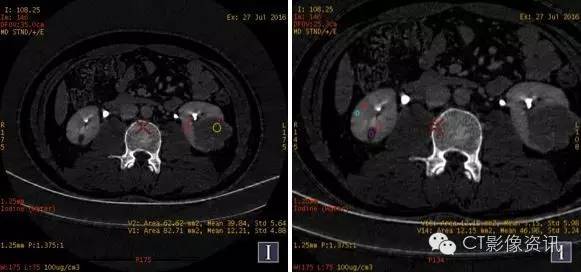

CT值单位:Hu 增强能谱扫描各期碘基物质图观察

左肾病灶(红色ROI 2)基物质碘含量与左肾髓质(黄色ROI 1 )相似,与左肾皮质(粉色ROI 3)存在较大差异。 右肾病灶基物质碘含量与右肾皮质、髓质纯在较大差异。且左、右肾病灶基物质碘含量明显不同。(见表二)

左、右肾病灶及肾实质基物质碘含量明显不同,其基物质碘含量亦不相同。(见表二)

表二:增强能谱扫描双肾及肾实质各期碘基物质测量结果

碘基物质测量(单位:100ug/立方厘米)